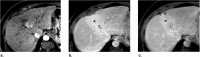

Computed tomography (CT) and magnetic resonance imaging (MRI) play critical roles for assessing treatment response of hepatocellular carcinoma (HCC) after locoregional therapy. Interpretation is challenging because posttreatment imaging findings depend on the type of treatment, magnitude of treatment response, time interval after treatment, and other factors. To help radiologists interpret and report treatment response in a clear, simple, and standardized manner, the Liver Imaging Reporting and Data System (LI-RADS) has developed a Treatment Response (LR-TR) algorithm. Introduced in 2017, the system provides criteria to categorize response of HCC to locoregional treatment (e.g., chemical ablation, energy-based ablation, transcatheter therapy, and radiation therapy). LR-TR categories include Nonevaluable, Nonviable, Equivocal, and Viable. LR-TR does not apply to patients on systemic therapies. This article reviews the LR-TR algorithm; discusses locoregional therapies for HCC, treatment concepts, and expected posttreatment findings; and illustrates LI-RADS treatment response assessment with CT and MRI.